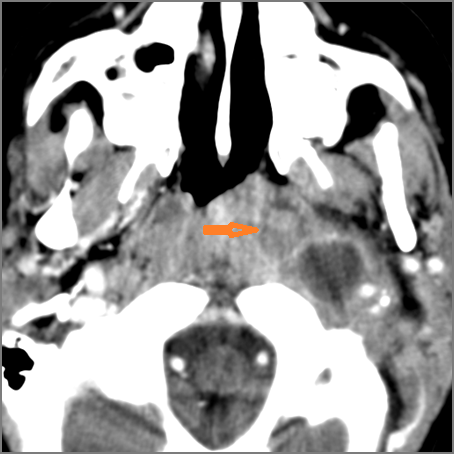

There is edema or abscess within the fat of the adjacent parapharyngeal and retropharyngeal space. [Yes/No]

There is edema or abscess within the adjacent parapharyngeal and retropharyngeal spaces. [Yes/No]